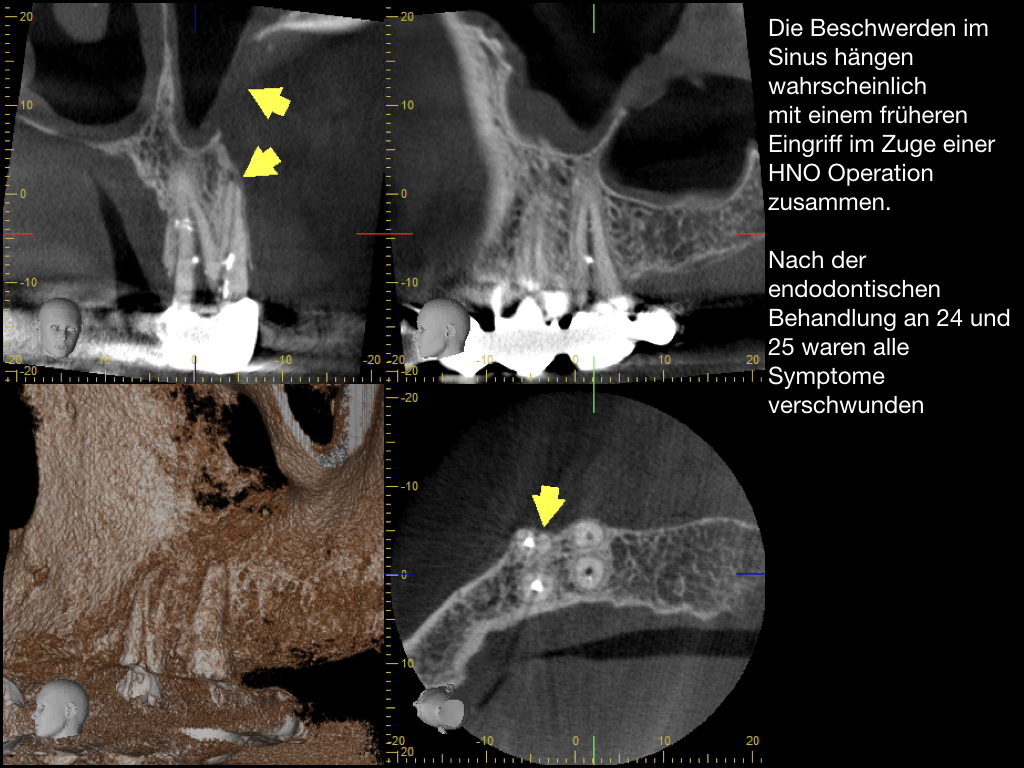

Es ist zu sehen … (2)